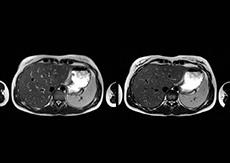

Motion reduction

“We also love MultiVane XD for motion reduction in imaging. We find this a huge step forward. We use it in the head, and of course in the upper abdomen, and the images are outstanding most of the time. And it can be combined with dS SENSE parallel imaging for speed.” “We have compared image quality of FLAIR with MultiVane XD versus FLAIR without MultiVane XD. In 15 of the 40 patients studied, we saw motion artifacts on plain FLAIR brain images. The FLAIR images with MultiVane XD were motion-free in 39 of 40 patients and showed slight motion artifacts in only one patient.”